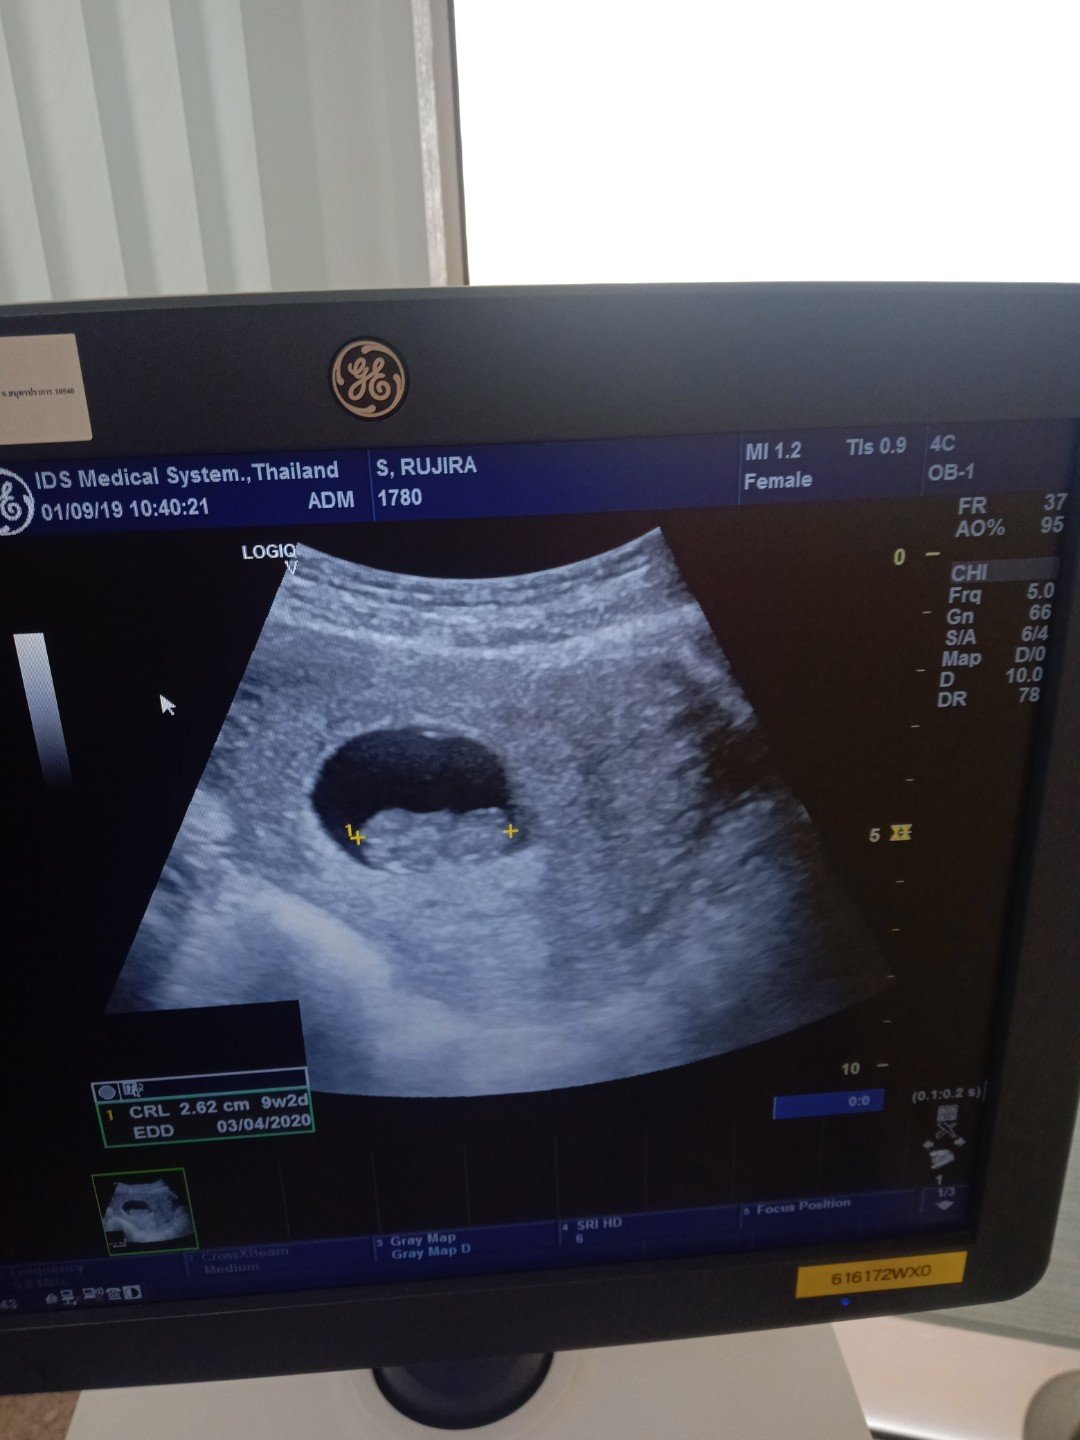

อัลตร้าซาวด์ช่วง 11W

ถ้าเครื่องมือหมอทันสมัยเหมือนคลินิค จะเห็นตั้งแต่6วีคค่ะ แต่จะให้ชัวและชัดต้องซาวช่วง8วีคค่ะแม่ ซาวคลินิค400-500บาท ซาวอย่างเดียวไม่รวมยาค่ะ บ้านนี้ซาวตอน8วีค4วัน

9วีคค่ะ ฝากคลีนิค